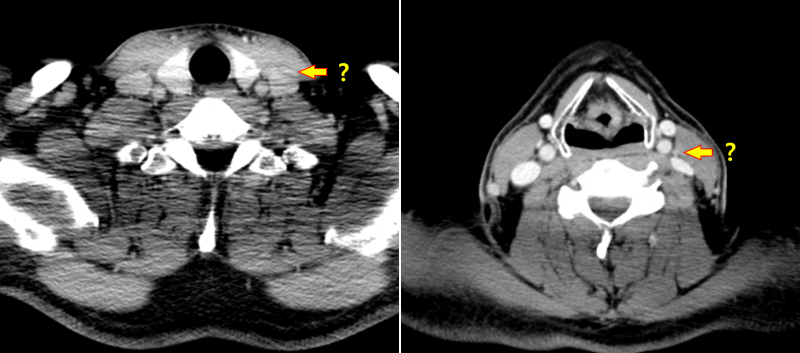

갑상선에 결절이 발견되면 옆 경부 림프절까지 잘 관찰해야 암 진단에도 도움이 되고 수술 범위를 정하는 데도 도움이 됩니다. 그런데 일반적으로 갑상선 암의 진단 환자도 옆 경부 림프절 검사를 게을리하는 일이 많습니다. 다른 병원에서 검사한 뒤 생큐 서울 이비인후과를 찾은 환자(712명)의 초음파 사진을 다시 검토한 결과 66%의 환자의 초음파 검사 사진에서 측 경부 검사가 빠지고 있었습니다.대학 병원 가운데 빅 5도 22%에서 탈락하며 빅 5를 제외한 대학 병원은 48%에서 탈락했어요.샌 환자들을 고마워서울 이비인후과에서 초음파 검사를 했는데, 약 6%의 환자에게서 측 경부 림프절 전이가 발견되었습니다.(해당 내용은 최근 대한 갑상샘 학회에서 발표했습니다.)관련의 증례를 하나 소개합니다.30세 남자 환자가 2년 전으로 건드리는 갑상선 결절에 대해서 상담하기 위해서, 생큐 서울 이비인후과- 내분비 내과 이·운정 원장 외래를 방문했습니다.2017-01-20대학 병원에서 초음파 검사와 총 생검을 실시했습니다만 옆 경부 림프절에 대해서는 전혀 검사를 벌이고 있지 않습니다. 당시 총 생검 결과는 양성 혹(benign follicular nodule이었습니다.*여기서 총 생검이 가는 바늘 흡입 세포 검사보다 항상 좋은 검사가 아님을 알 수 있습니다. (중략)2019-08-03시행한 고마워서울 이비인후과 초음파 사진은 다음과 같습니다.

그 환자의 수술 리뷰는 아래에 있습니다. https://cafe.naver.com/thanqseoul/1335 감사합니다.